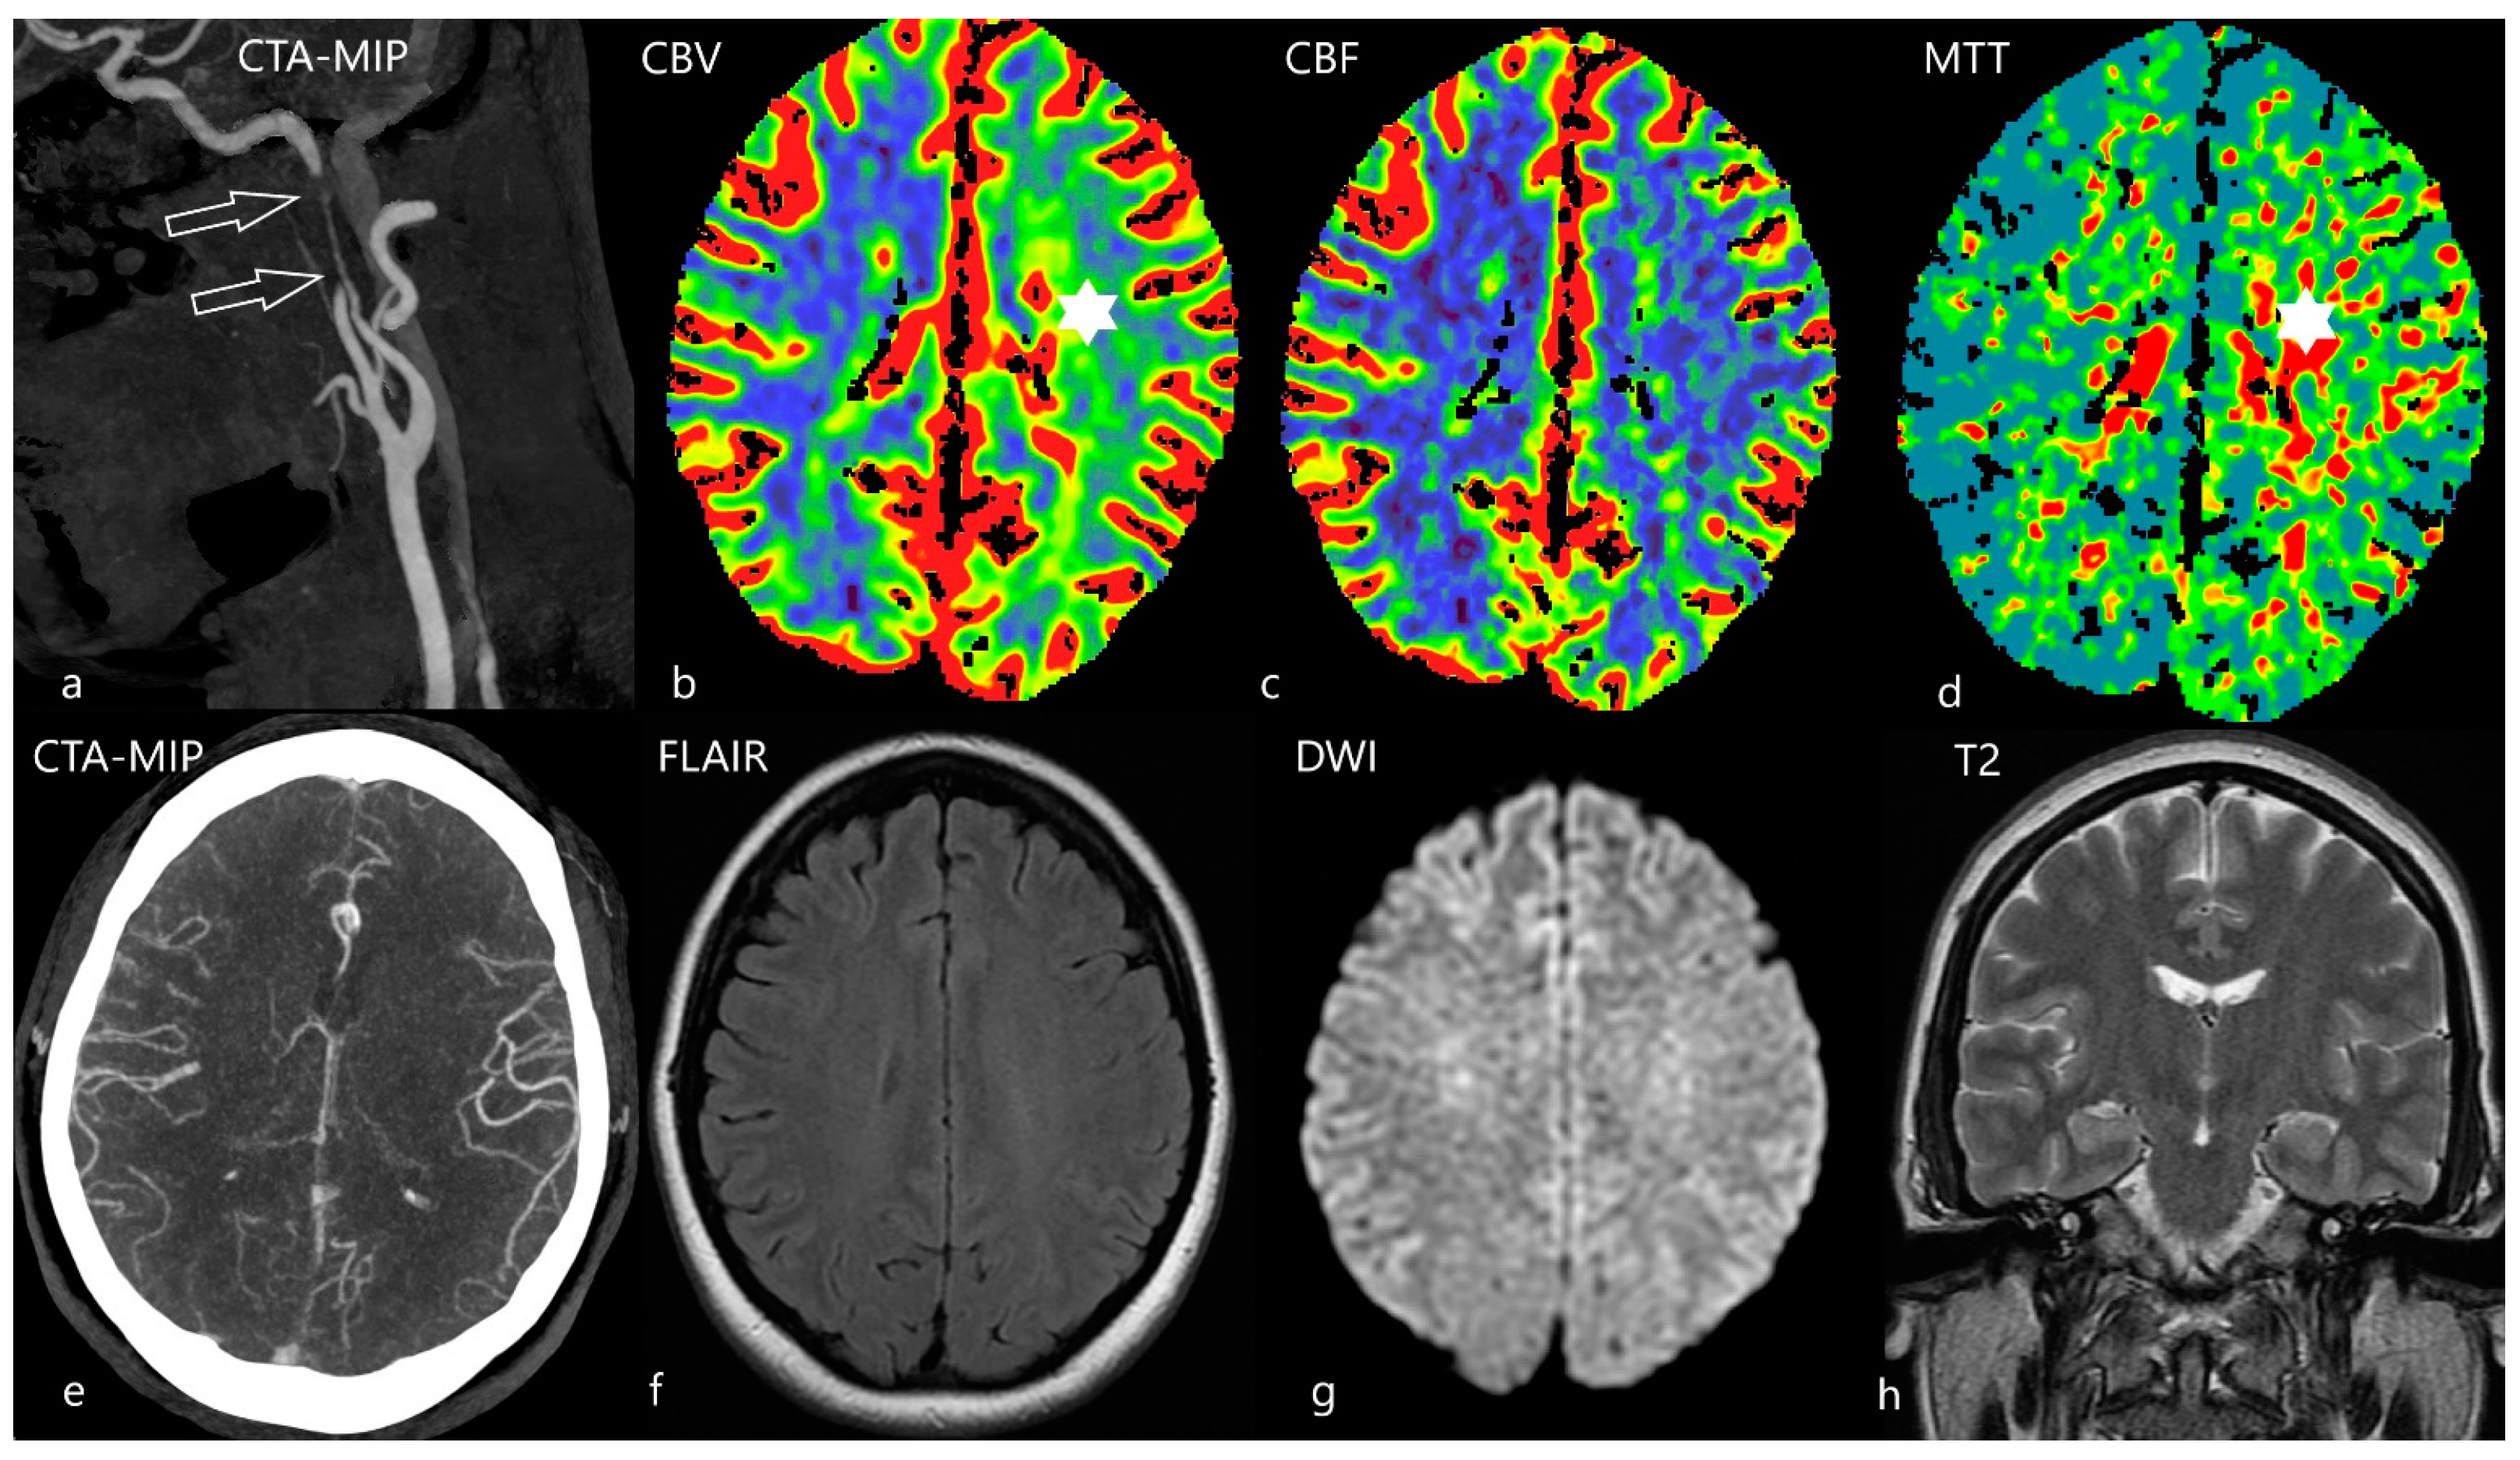

5. The Third Task: To Estimate the Ischemic Core

- Nagel, S.; Herweh, C.; Pfaff, J.A.R.; Schieber, S.; Schönenberger, S.; Möhlenbruch, M.A.; Bendszus, M.; Ringleb, P.A. Simplified selection criteria for patients with longer or unknown time to treatment predict good outcome after mechanical thrombectomy. J. Neurointerv. Surg. 2019, 11, 559–562. [Google Scholar] [CrossRef]

- Konstas, A.A.; Minaeian, A.; Ross, I.B. Mechanical Thrombectomy in Wake-Up Strokes: A Case Series Using Alberta Stroke Program Early CT Score (ASPECTS) for Patient Selection. J. Stroke Cerebrovasc. Dis. 2017, 26, 1609–1614. [Google Scholar] [CrossRef]

- Kremenova, K.; Holesta, M.; Peisker, T.; Girsa, D.; Weichet, J.; Lukavsky, J.; Malikova, H. Is limited-coverage CT perfusion helpful in treatment decision-making in patients with acute ischemic stroke? Quant. Imaging. Med. Surg. 2020, 10, 1908–1916. [Google Scholar] [CrossRef]